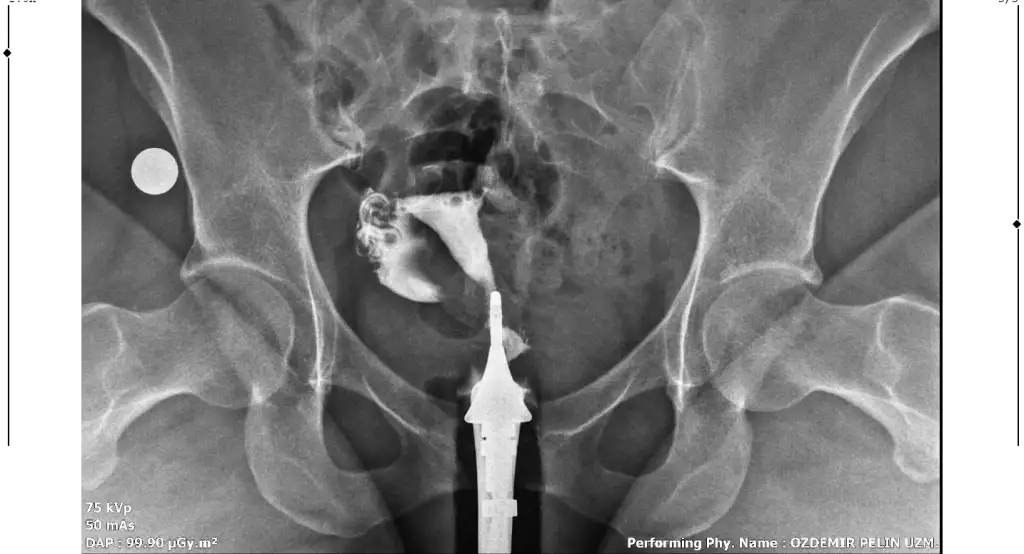

Merhaba, sağlıklı rahim gorseli ile kiyaslaninca sanki üstten biraz basık ama endişelenmeyin benim direk Y di belki çekim açısından olabilir, sizde sadece tüpleri anlayamadim dağılmış sanki açık tikaniklikda yok gibiMerhaba benim rahim filmim bu şekilde bir rapor oluşturulmadı filmi bugün çekildim doktora da gosteremedim. Yorumlanabilir misiniz?

Çok teşekkür ederim cevabınız içinMerhaba, sağlıklı rahim gorseli ile kiyaslaninca sanki üstten biraz basık ama endişelenmeyin benim direk Y di belki çekim açısından olabilir, sizde sadece tüpleri anlayamadim dağılmış sanki açık tikaniklikda yok gibi

Sizin yorumunuzu görünce bende hidrospenks baktım da sanki sağ tarafta boğum var gibi ama tek tüple de gebelik oluşuyor zaten benimde tıkalı malesef, yinede endişelenmeyin sakın korkuyorumda yorum yaparken yanlış anlaşılırim üzerim diyeGenişleme olabileceği söylendi yani sıvı olabilir dendi. Hidrosalpenks oluyor o var gibi geldi sanki bana

Anlayışınız için çok teşekkür ederim. Bakalım doktora gösterince net sonucu öğrenirim. Çok teşekkür ederim tekrardan.Sizin yorumunuzu görünce bende hidrospenks baktım da sanki sağ tarafta boğum var gibi ama tek tüple de gebelik oluşuyor zaten benimde tıkalı malesef, yinede endişelenmeyin sakın korkuyorumda yorum yaparken yanlış anlaşılırim üzerim diye

Ben de geçen hafta çektirdim HSG filmi. Raporum bugün oluştu ama anladığım kadarıyla sağ tüp açık sol tüp kapalı sanırım. Bana da yorumlama konusunda yardımcı olabilir misiniz? 4 senelik evliyim ve bebek sahibi olamadık, gebelik de hiç oluşmadı. Pcos'tan mustaribim. Tavsiyelerinizi alabilirim.

Merhaba bana da hidroselpenks gibi geldi çok hafif boğum var doktorunuzun yorumu ne oldu acabaMerhaba benim rahim filmim bu şekilde bir rapor oluşturulmadı filmi bugün çekildim doktora da gosteremedim. Yorumlanabilir misiniz?

Canım rahim yapısı güzelmişT tubiikk Ekledim görüntüleri, teşekkür ederim.

Sağ tüpün açık sol tüpün kapalıymış ben öyle anladım görüntüde de biri kapalı gözüküyor zaten